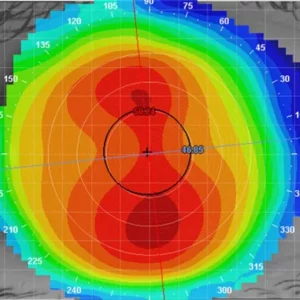

- Jak prawidłowo wykonać topografię rogówki?

- Jak analizować mapy rogówki pod kątem soczewek ortokorekcyjnych?